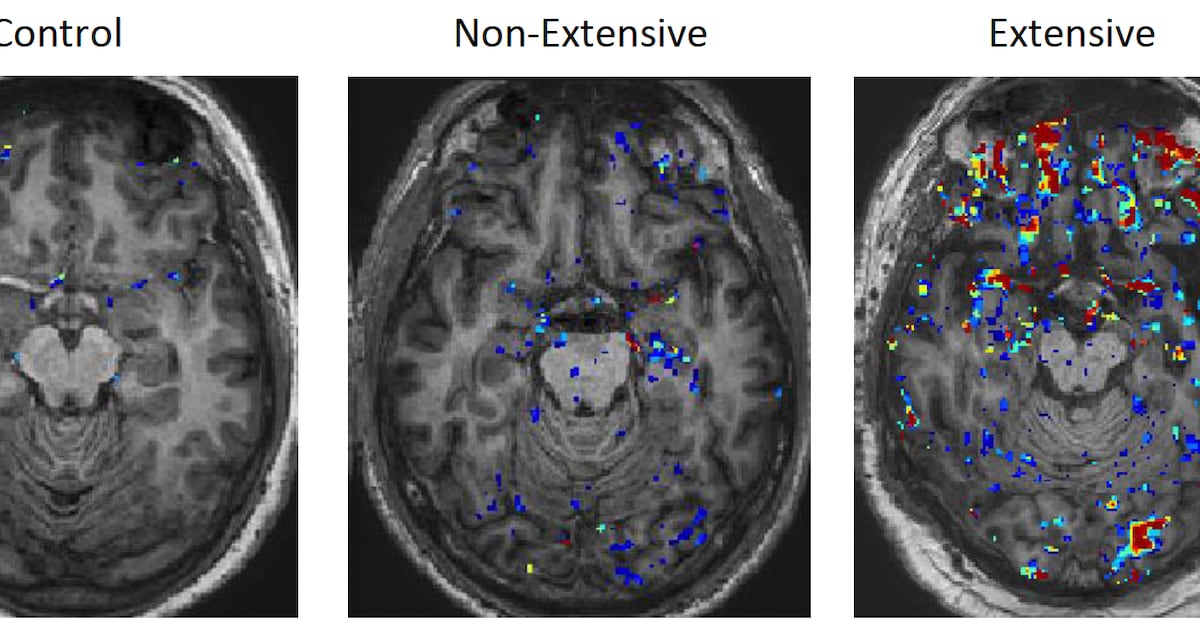

Pol theta enzyme identified as key driver of cancer resilience

A cancer drug target already being investigated in clinical trials turns out to be doing something even more consequential than researchers realized. Scientists at Scripps Research have discovered that the enzyme Pol theta (Polθ)…